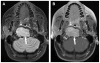

Cross-sectional imaging plays an important role in the evaluation of the retropharyngeal space (RPS) and the prevertebral space (PVS). Because of their deep location within the neck, lesions arising within these spaces are difficult, if not impossible, to evaluate on clinical examination. This article details the cross-sectional anatomy and imaging appearances of primary and secondary diseases involving the RPS and PVS, including metastasis and spread from adjacent spaces. The role of image-guided biopsy is also discussed.